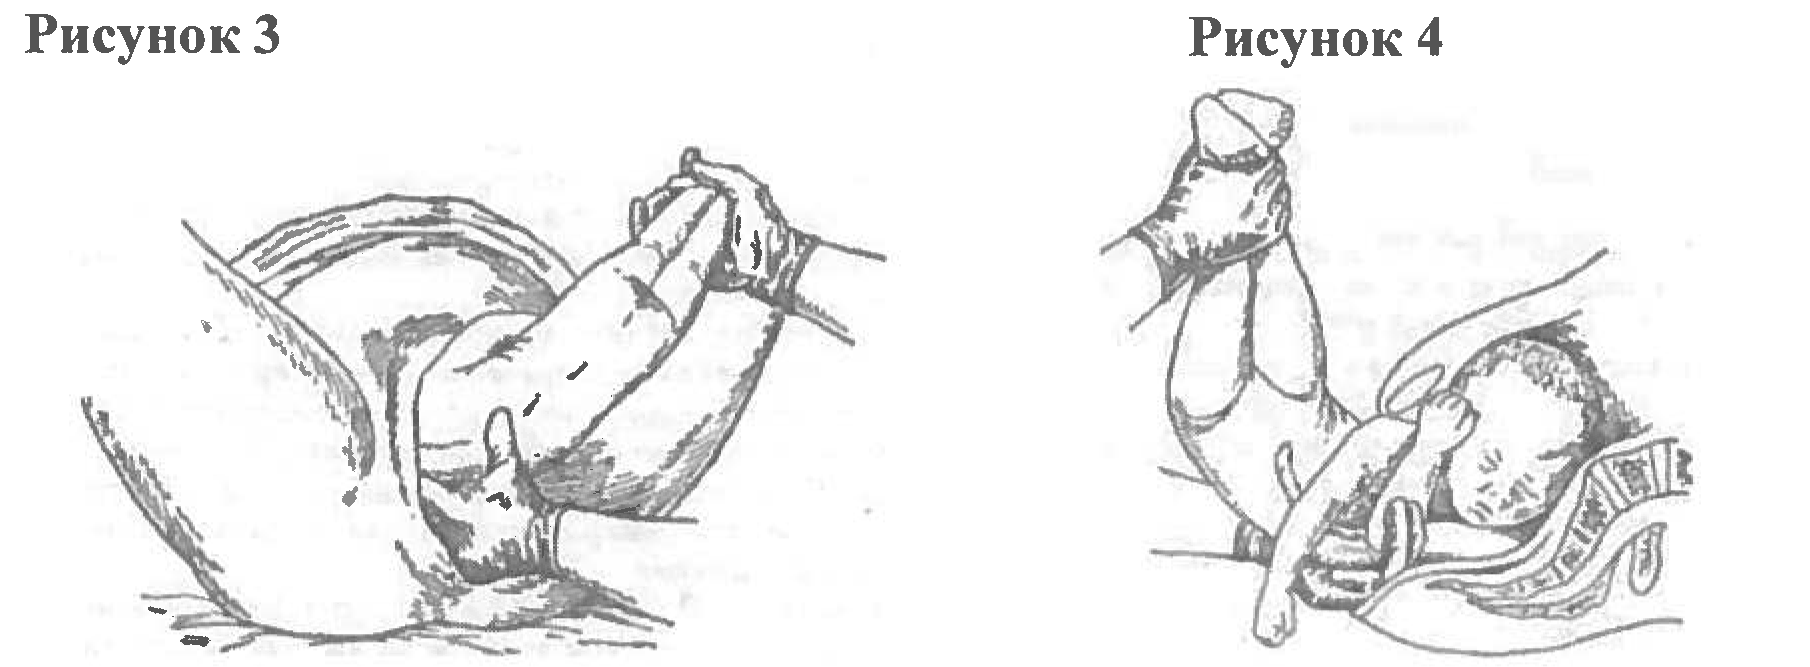

Метод Цовьянова при ягодичном предлежании

Пособие по Морисо Левре Лашапель

Рождение ребенка в тазовом предлежании

Первый момент биомеханизма родов при тазовом предлежании